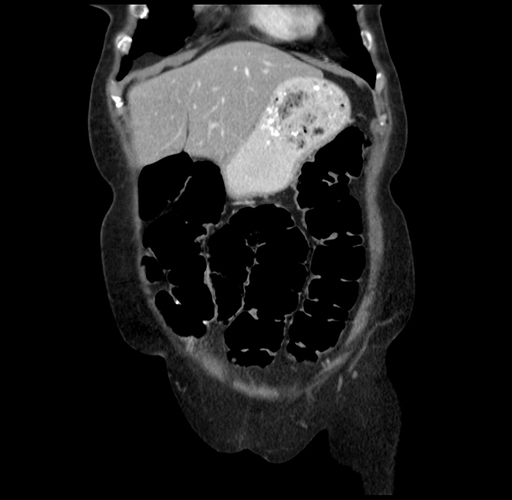

Pre-Chemo: Coronal Venous

Coronal Venous